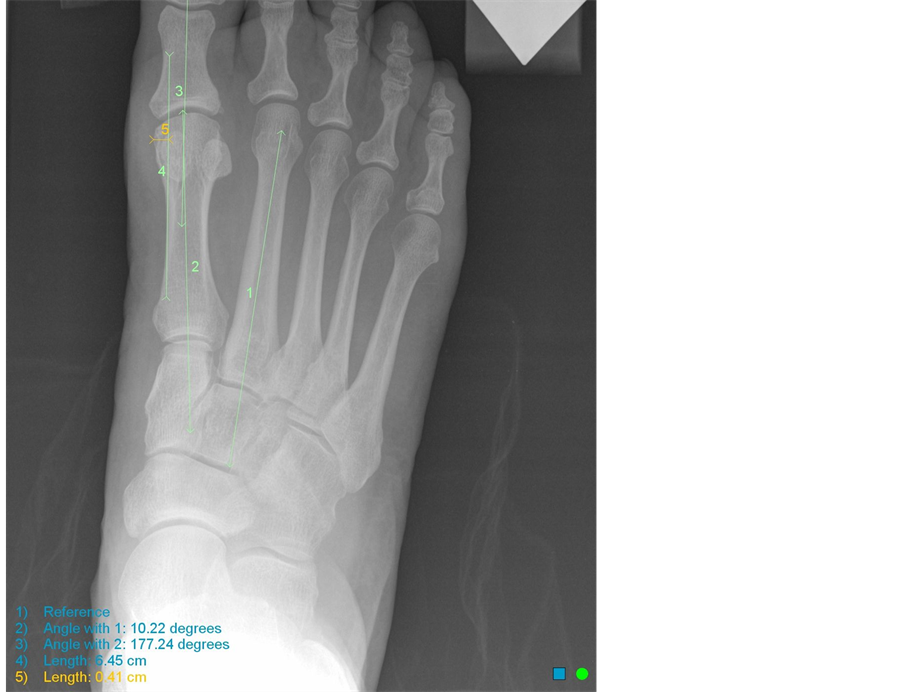

From www.researchgate.net

The measurement of the valid width of the first metatarsal. The Medial Eminence Toe As these authors argue, surgeons may resect the medial eminence to facilitate other bunion procedures, prevent potential complications. As these authors argue, surgeons may resect the medial eminence to facilitate other bunion procedures, prevent potential complications. Halluces valgi) is a fixed abduction of the first metatarsophalangeal joint of the great toe. Characterized by a small bump at the medial eminence,. Medial Eminence Toe.

From file.scirp.org

A Method for Measurement of the Hypertrophic First Metatarsal Medial Medial Eminence Toe Halluces valgi) is a fixed abduction of the first metatarsophalangeal joint of the great toe. Characterized by a small bump at the medial eminence, the part of the foot where the inside edge of the big toe is joined to the foot. As these authors argue, surgeons may resect the medial eminence to facilitate other bunion procedures, prevent potential complications.. Medial Eminence Toe.

From www.scirp.org

A Method for Measurement of the Hypertrophic First Metatarsal Medial Medial Eminence Toe As these authors argue, surgeons may resect the medial eminence to facilitate other bunion procedures, prevent potential complications. Characterized by a small bump at the medial eminence, the part of the foot where the inside edge of the big toe is joined to the foot. Halluces valgi) is a fixed abduction of the first metatarsophalangeal joint of the great toe.. Medial Eminence Toe.